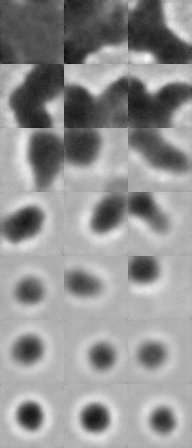

To visualize how this progression manifests in the output quality, we highlight three training epochs in Figure 4(a), from which we sample and present generated images in Figure 4(c) and Figure 4(d). As shown in these figures, early-stage outputs (e.g., epoch 5 or 10) are low-fidelity, often exhibiting incomplete particle shapes, indistinct boundaries, and missing structural features. In contrast, by epoch 50, the models generate more realistic and coherent particle images, capturing essential characteristics such as spherical morphology, texture, and transparency. This visual progression illustrates how the diffusion models incrementally refine their internal representation of sub-visible particle structure as training advances.

Figure 2 provides a visualization of the denoising process in the reverse diffusion trajectory. Starting from pure Gaussian noise, the model progressively refines the image over 1,000 steps in our setup, gradually introducing particle-specific structures in a visually interpretable manner. To illustrate this process, we present six representative images along the trajectory. This progression highlights the ability of the generative model to recover subtle class-specific features, such as the halo effect in air bubbles or the smooth texture in silicone oil droplets, reinforcing confidence in the utility of these samples for downstream classification.

The visual quality of the generated samples from the fully trained models is illustrated in Figure 5. As can be seen, the synthesized images closely resemble real FIM images, capturing essential morphological features such as shape irregularities, texture, and transparency. Notably, the generated air bubble images preserve the circular and semi-translucent characteristics typically observed in real samples, while silicone oil droplets exhibit the distinct contour and scattering patterns that differentiate them from other SvP types. These qualitative results suggest that our diffusion models effectively learns the underlying distribution of each particle type, despite the low data regime.